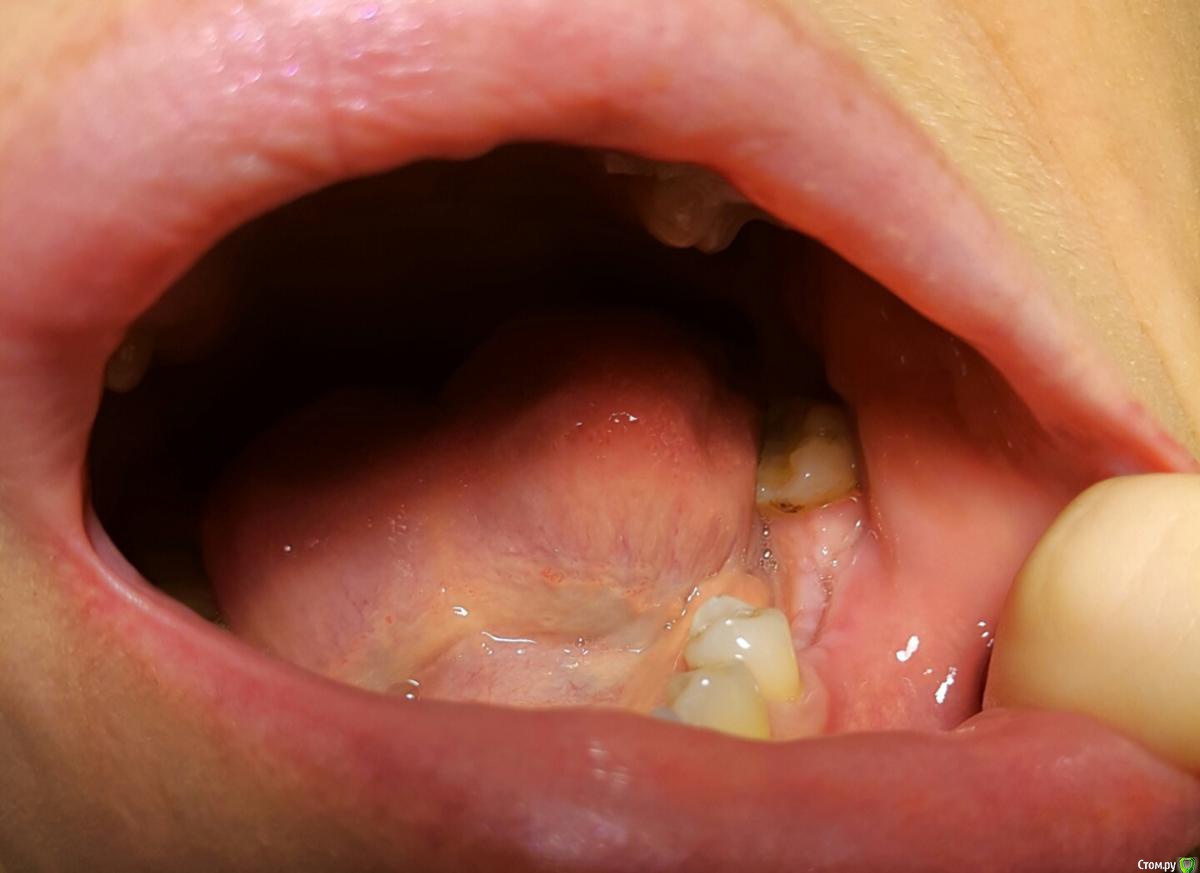

june10 Опубликовано 17 марта, 2018 Поделиться Опубликовано 17 марта, 2018 (изменено) Добрый день! Имплантацию сделали 26 февраля,через несколько дней после снятия швов опухла десна и начала выделяться жидкость при надавливании языком. Боли и температуры нет, десна обычного цвета. Врач посмотрел снимок онлайн сказал что в кости воспаления нет и назначил полоскания и антибиотики. Имплантация была с био осс. Что делать, ехать к врачу? Он в другом городе или ждать само пройдет ? Изменено 17 марта, 2018 пользователем june10 Ссылка на комментарий

Большой Зеленый Опубликовано 17 марта, 2018 Поделиться Опубликовано 17 марта, 2018 С виду все обычно . Ссылка на комментарий